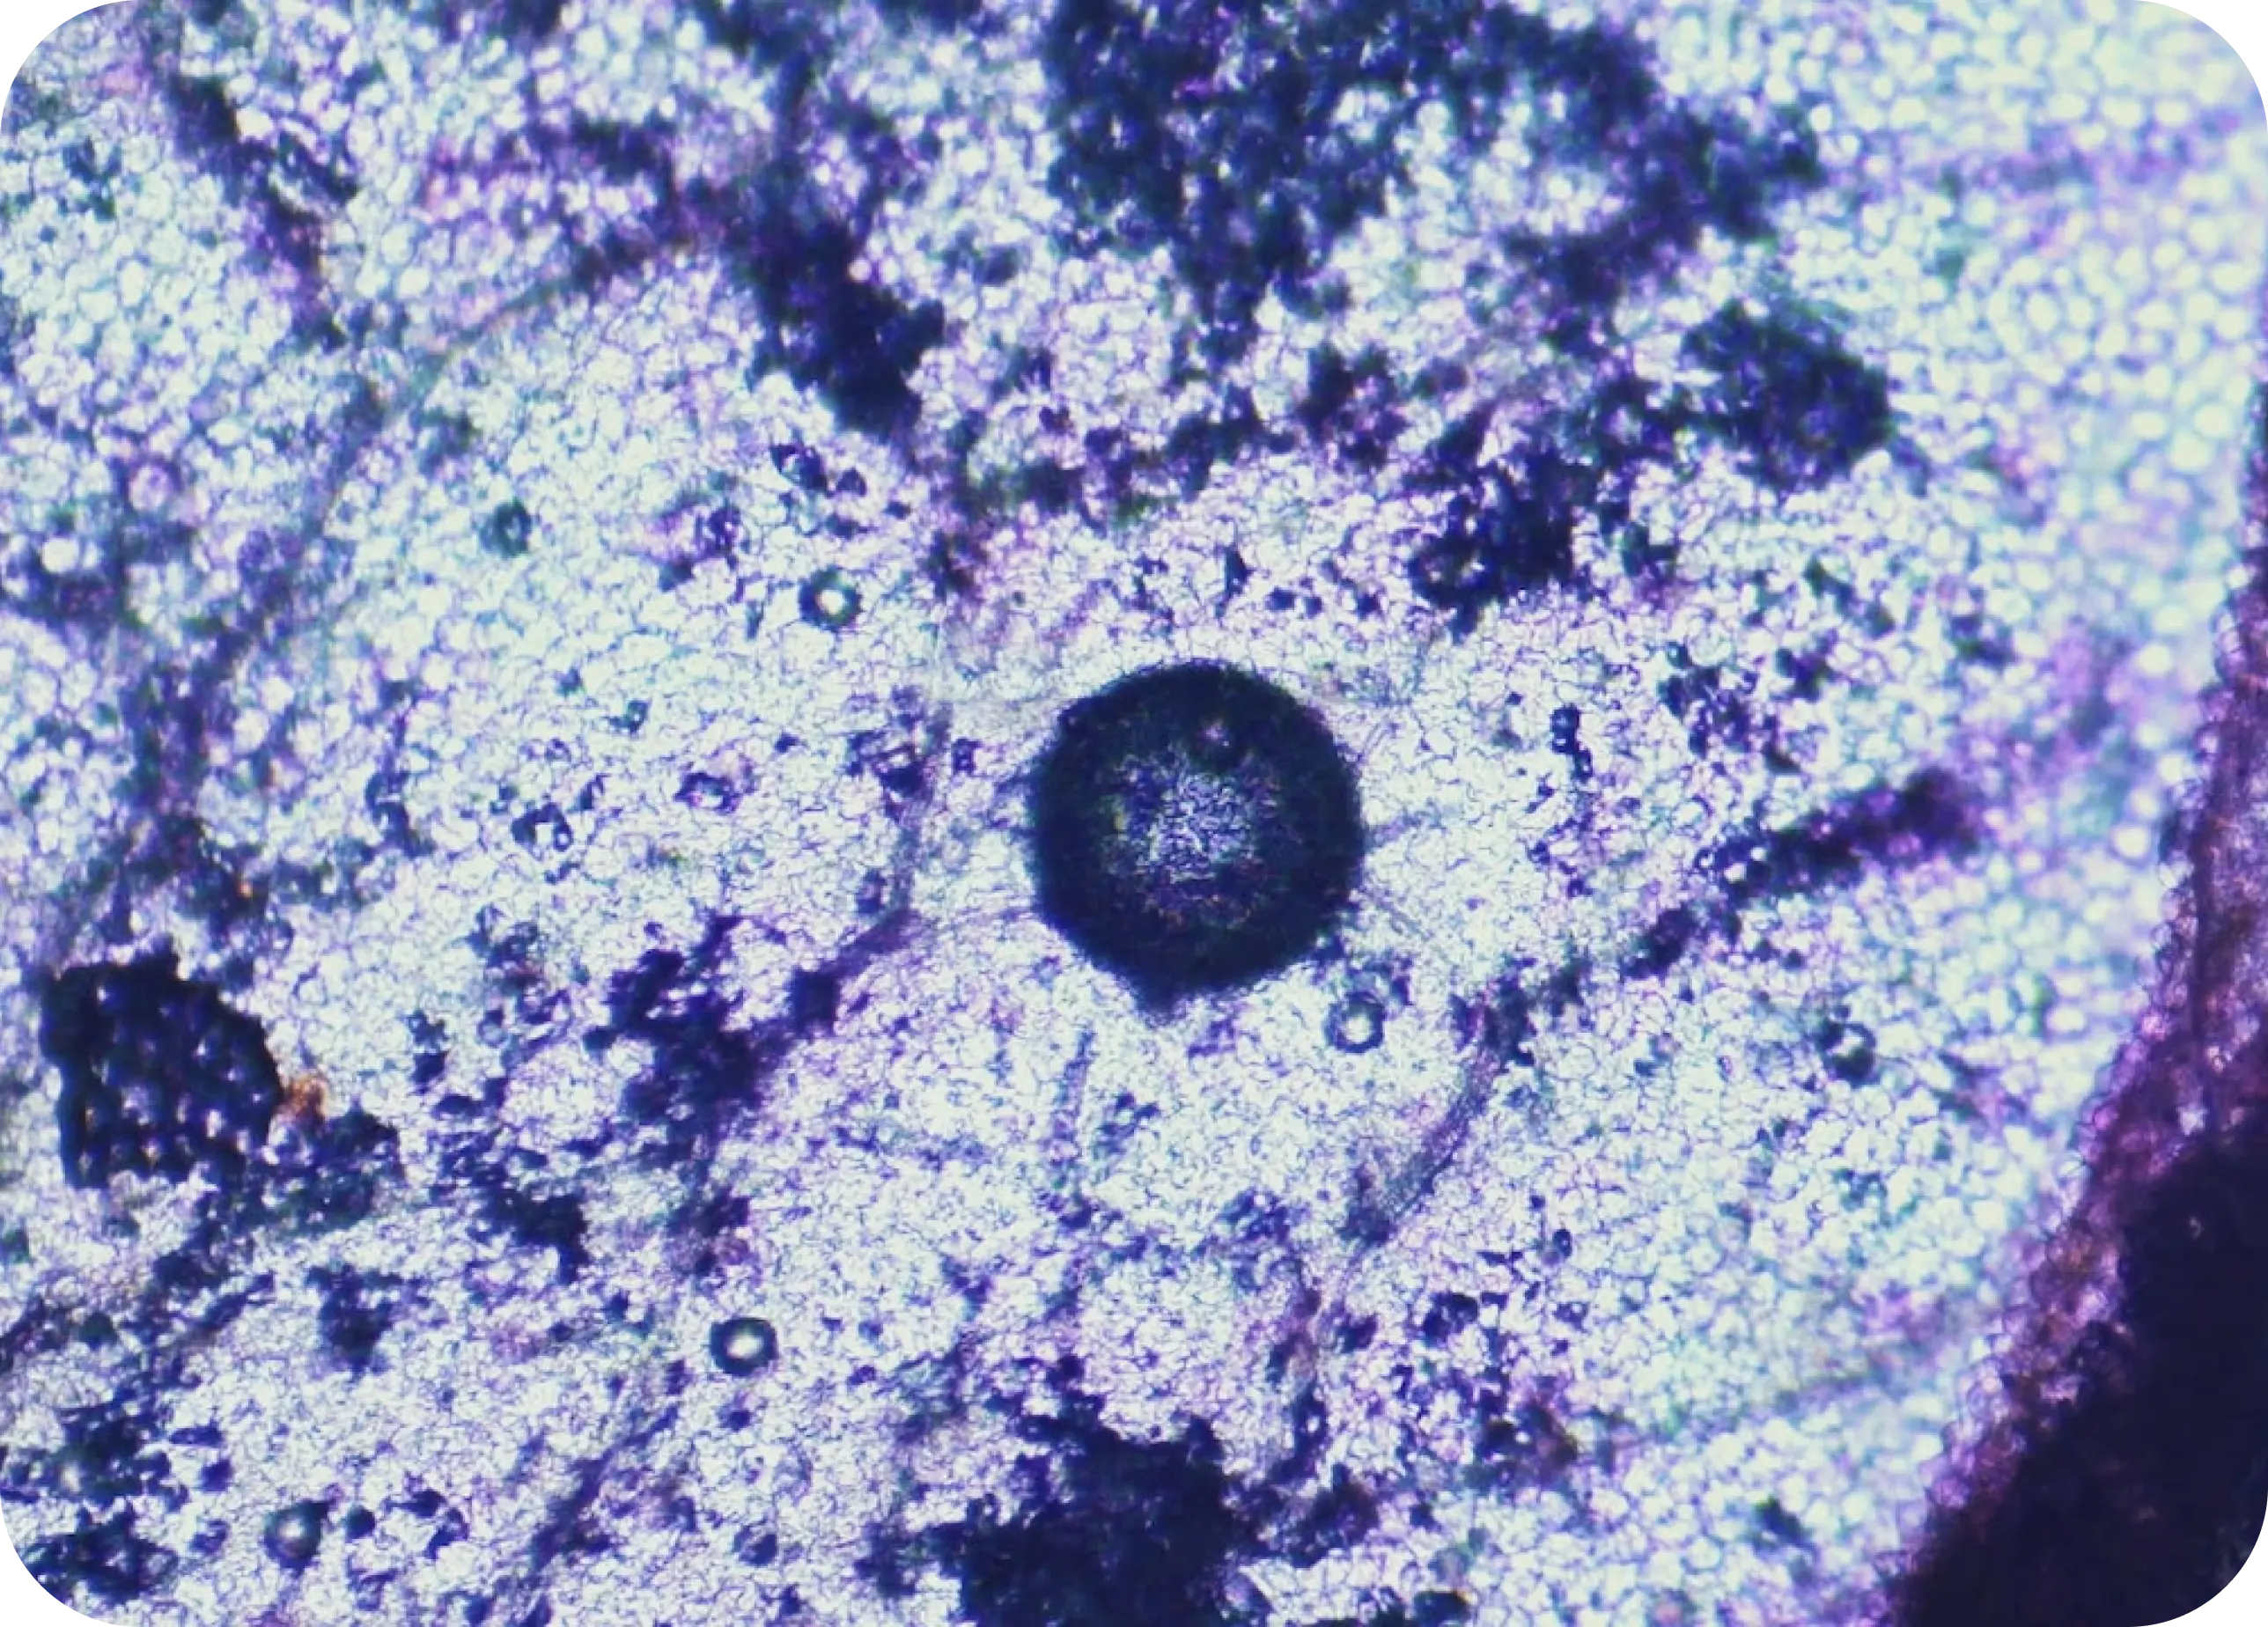

Lab Tests

We test what matters

Scientifically proven,

made just for you

We use your biomarkers to pinpoint nutrient gaps and create a custom formulation. Precision supplements uniquely support your body and evolve with your health.